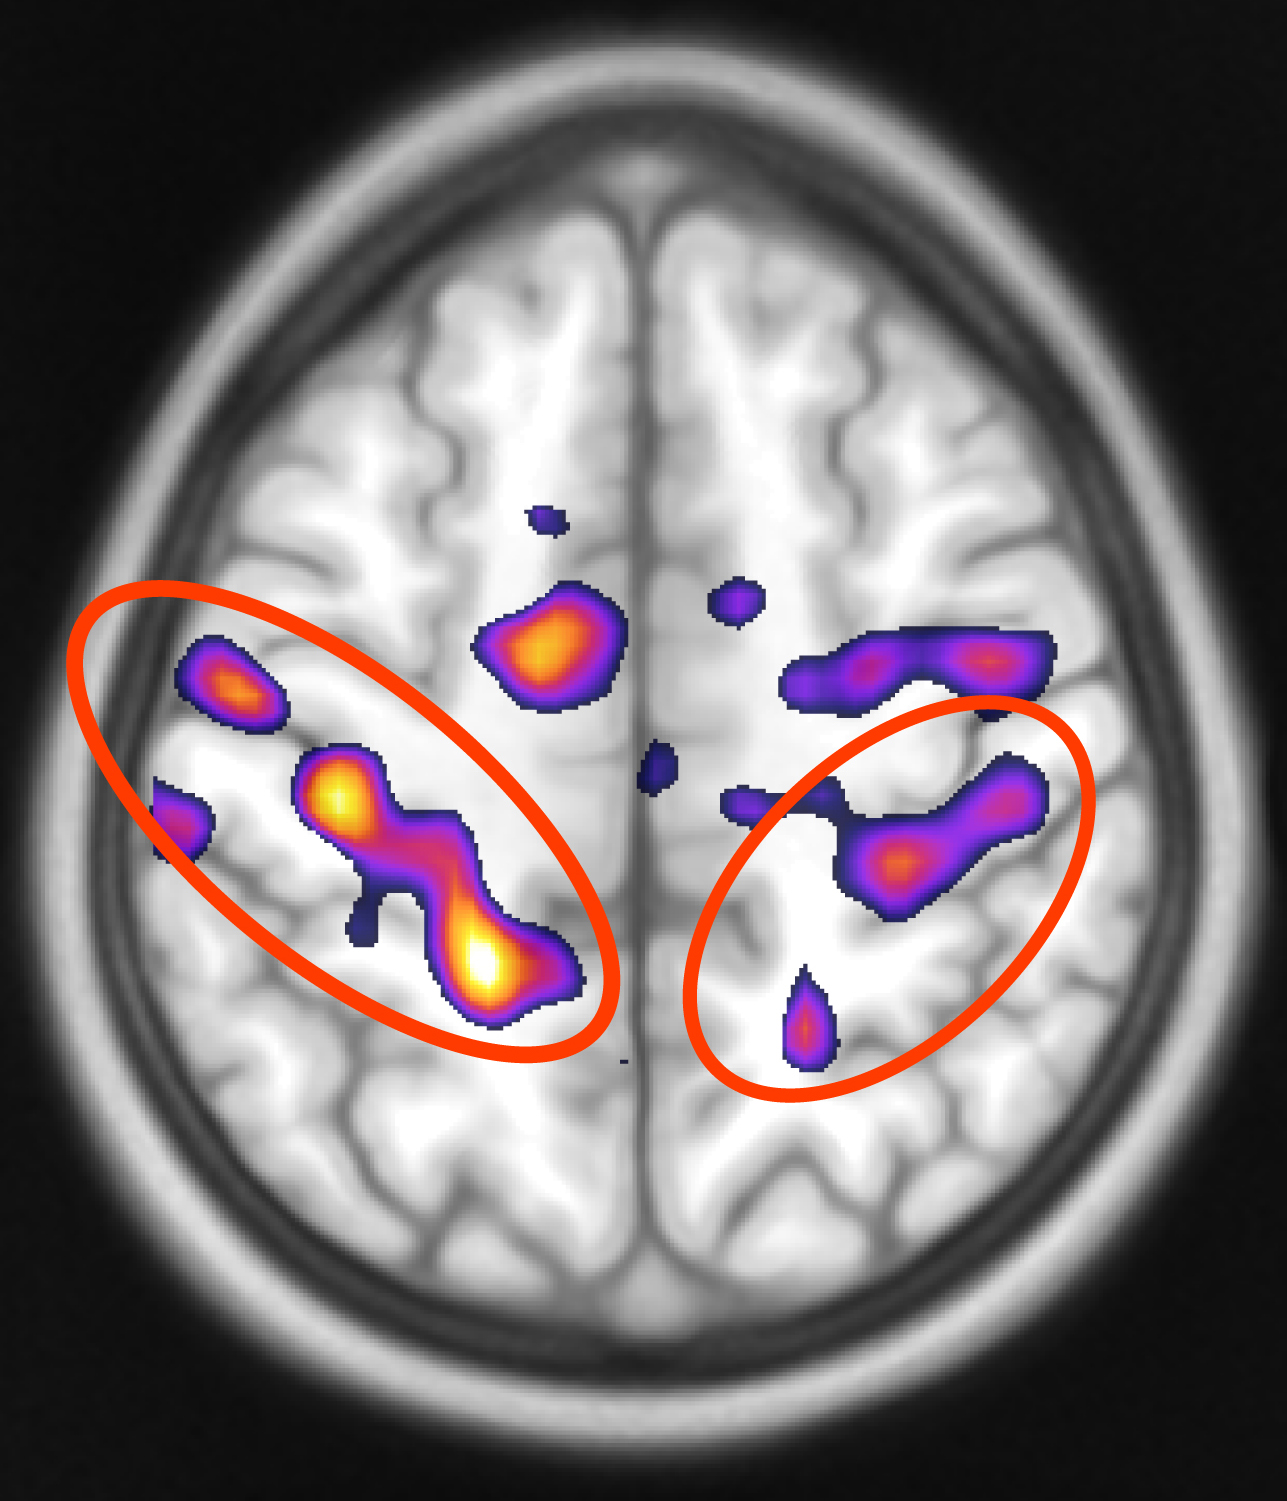

„Die emotionale Überempfindlichkeit von Borderline-Patientinnen wird begleitet von einer erhöhten Aktivität spezifischer Spiegelneuronen“, erklärt Professor Roberto Viviani. Der Bildgebungsexperte forscht an der Klinik für Psychiatrie und Psychotherapie III der Universität Ulm zur Emotionsregulierung. Spiegelneuronen sind im präfrontalen und im sensorischen Cortex des Gehirns zu finden. Das Besondere an diesen Neuronen: Diese Nervenzellen werden bereits durch die Beobachtung von Handlungen und die Fremdwahrnehmung von Gefühlen stimuliert. Sie sind damit entscheidend für das Lernen durch Nachahmung und das Nacherleben von Emotionen. Als eine Art Resonanzsystem im Gehirn reagieren diese besonderen Nervenzellen sehr sensibel auf die Gefühle und Stimmungen anderer, weshalb sie nicht nur für die Empathie-Fähigkeit des Menschen entscheidend sind, sondern auch eine Schlüsselrolle bei der so genannten emotionalen Ansteckung spielen. Die Ulmer Forscherinnen aus der Arbeitsgruppe von Viviani haben nun in Zusammenarbeit mit Wissenschaftlerinnen aus Österreich herausgefunden, dass BPS-Patientinnen besonders stark auf Szenen von Verlust und Trauer reagieren. Wie die Aufnahmen aus der magnetresonanztomografischen Untersuchung (MRT) zeigten, waren bestimmte Areale im Spiegelneuronensystem deutlich stärker aktiviert als in der „normalen“ Kontrollgruppe, wenn sie mit Verlust konfrontiert wurden. Entwickelt wurden die Szenen am Institut für Psychologie der Universität Innsbruck von Dr. Karin Labek. „Dieser Befund könnte erklären, warum Menschen, die unter einer Borderline-Störung leiden, für solche negativen Gefühle so empfänglich sind und so extrem darauf reagieren“, so Labek. Bereits bekannt ist, dass überdurchschnittlich viele Borderline-Patientinnen und Patienten auch unter Depressionen leiden.

Ein weiterer Befund, der bei der Untersuchung zutage trat, war für das Forscher-Team noch überraschender. So war auf den MRT-Aufnahmen im Vergleich mit der gesunden Kontrollgruppe deutlich zu erkennen, dass es weitere Unterschiede im präfrontalen Cortex gab. Hier zeigte sich, dass bei den BPS-Patientinnen ein Bereich weitaus weniger stark aktiviert war, der für die kognitive Beurteilung von Gefühlszuständen Anderer entscheidend ist. Dieser Bereich ist für die sogenannte „Mentalisierung“ verantwortlich, also für die reflektive Einstufung von Gefühlswahrnehmungen. Diese Mentalisierung braucht es, um die Absichten und Motivationen anderer Menschen einschätzen zu können. „Dieser Befund könnte erklären, warum es den Borderline-Betroffenen so schwer fällt, sich in andere hineinzuversetzen und deren Perspektive zu übernehmen“, meint PD Dr. Zrinka Sosic-Vasic, Erstautorin der im Journal „NeuroImage: Clinical“ veröffentlichten Studie.